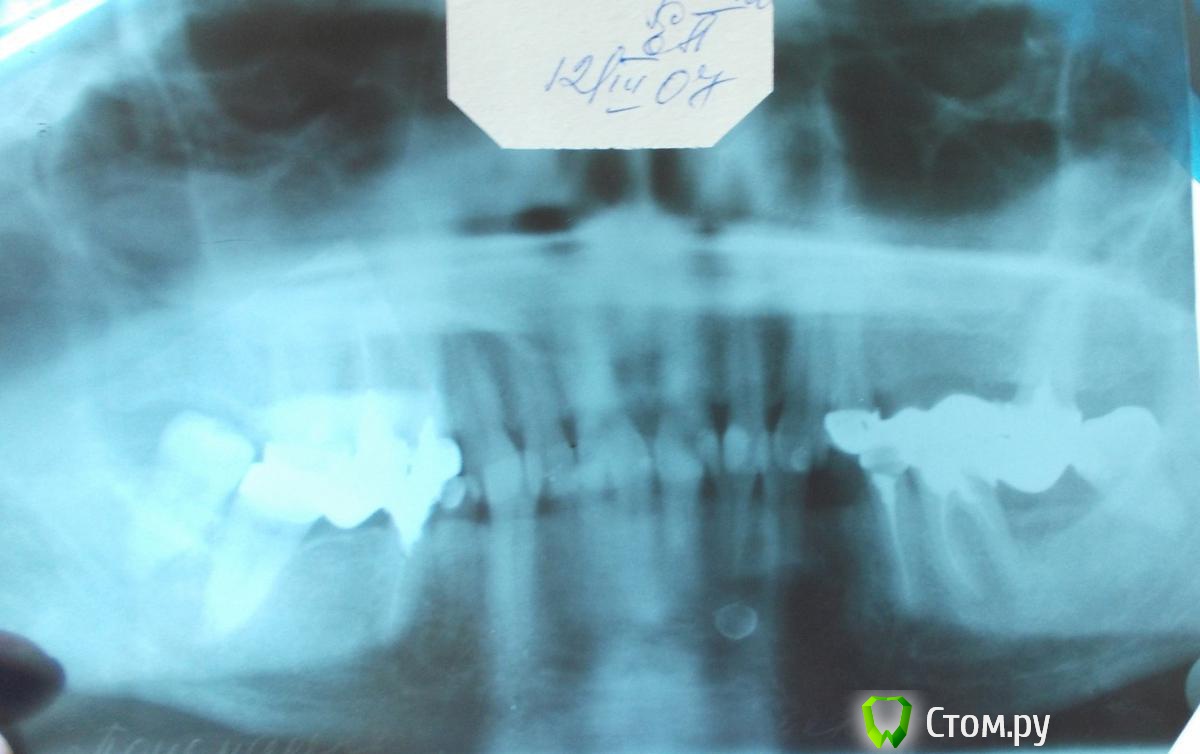

Helenka Опубликовано 21 сентября, 2014 Поделиться Опубликовано 21 сентября, 2014 Добрый день! Помогите пожалуйста найти другой способ лечения, от предложенного мне на днях. История болезни. В сентябре 2006 года была обнаружена киста зуба 4.4. Врачи в городской поликлинике предложили удалить три зуба и операцию в ЧЛХ. Конечно я не согласилась, пошла к частному стоматологу, она предложила лечение. Не могу сейчас описать какое, я не специалист. Мы удалили только один этот зуб и через него закладывали лекарство, в течении полугода это длилось. Сделали контрольный снимок в марте 2007 г. Врач сказал, что все вылечили. После чего я протезировалась. Все эти годы не ходила к врачу, хватило того полугода, да и абсолютно ничего не беспокоило. Недавно она мне позвонила и предложила сделать контрольный снимок. Снимок сделала. Она в ужасе. Отправила в ЧЛХ. Там сказали, что удалить нервы с нижних передних 6 зубов и будут делать операцию. А они у меня здоровые! Прикрепляю все снимки. Может надо вначале пройти какое-нибудь обследование, почему киста такая большая? Может ее уменьшить каким-нибудь лекарством? Есть ли у нас в России клиники занимающиеся лечением таких кист, а не вырезанием половины челюсти? Заранее благодарю за ответы. Ссылка на комментарий

dr-krasnov Опубликовано 21 сентября, 2014 Поделиться Опубликовано 21 сентября, 2014 Киста такая большая, потому что росла 7 лет. Лечением таких больших кист занимаются хирурги, например в НИИ Стоматологии и челюстно-лицевой хирургии в Москве. 2 Ссылка на комментарий